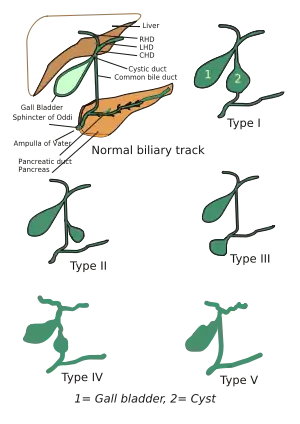

| Different types of choledochal cysts | |

They were classified into 5 types by Todani in 1977.[3]

Classification was based on site of the cyst or dilatation. Type I to IV has been subtyped.

- Type I: Most common variety (80-90%) involving saccular or fusiform dilatation of a portion or entire common bile duct (CBD) with normal intrahepatic duct.

- Type II: These cysts are present as an isolated diverticulum protruding from the CBD.

- Type III or Choledochocele: Arise from dilatation of duodenal portion of CBD or where pancreatic duct meets.

- Type IVa: Characterized by multiple dilatations of the intrahepatic and extrahepatic biliary tree.

- Type IVb: Multiple dilatations involving only the extrahepatic bile ducts.

- Type V: Cystic dilatation of intrahepatic biliary ducts without extrahepatic duct disease. The presence of multiple saccular or cystic dilations of the intrahepatic ducts is known as Caroli's disease.[4]

- Type VI: An isolated cyst of the cystic duct is an extremely rare lesion. Only single case reports are documented in the literature. The most accepted classification system of biliary cysts, the Todani classification, does not include this lesion. Cholecystectomy with cystic duct ligation near the common bile duct is curative.[5]